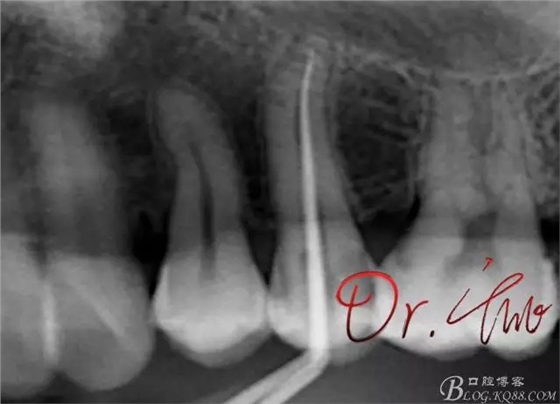

試主尖,近中頰側(cè)形成臺階

試主尖,近中頰側(cè)再次拍片查看臺階位置及確定長度

試主尖,近中頰側(cè)試主尖,此時手用銼02錐度的已擴到30號,可以明顯感覺到臺階位置,挫預(yù)彎后找好正確位置可順利到達根尖,但是機用銼就是下不去,也是郁悶

試主尖,在30號02錐度K挫到達根尖后,用02錐度牙膠尖找準(zhǔn)位置,進行試尖